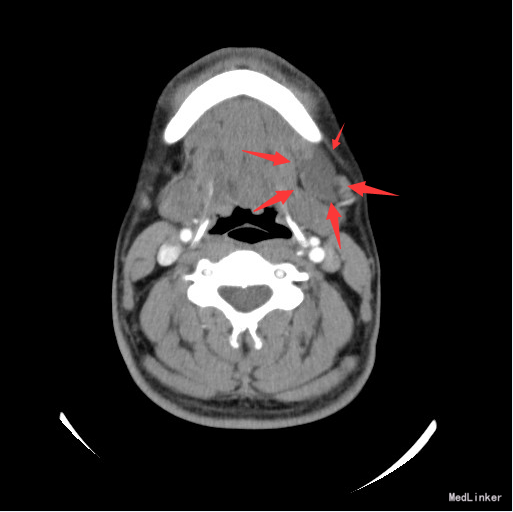

查体:左颌下可触及一肿物,大小约6*3cm,质软,无压痛,与周围组织境界不清。 辅查:颈部螺旋CT:左侧颌下三角区良性囊性肿块,考虑腮裂囊肿可能性大。

诊断:腮裂囊肿 治疗:排除手术禁忌,于全麻下行左颈深部肿物切除+颌下腺及舌下腺切除+颌下淋巴清扫术。术程顺利,术后予以消肿止痛、改善循环、预防感染等治疗,恢复满意。

随访:病理:(颌下及颏下肿物)组织内见一囊肿,囊壁由肉芽组织构成,未见内衬上皮,内含粘液,考虑为粘液囊肿。 讨论:鳃裂囊肿是由胚胎发育中鳃裂残余上皮组织发生的一种先天畸形。胚胎第4周1~4对鳃弓形成,鳃弓之间的腔隙为鳃裂,在胚胎第9周闭 合,如不闭合,残余上皮组织形成鳃裂囊肿。以第二鳃裂囊肿最为常见,约占90%。发生部位依次为耳、腮腺周围;颌下腺外侧、颈动脉间隙外侧、胸锁乳突肌前内侧、上颈后三角区、中、下颈沿胸锁乳突肌前缘,CT表现为沿胸锁乳突肌走行的圆形或类圆形囊性肿块,边界清晰,形态规则。伴有感染时囊壁增厚,边界不清,增强扫描囊壁明显强化。